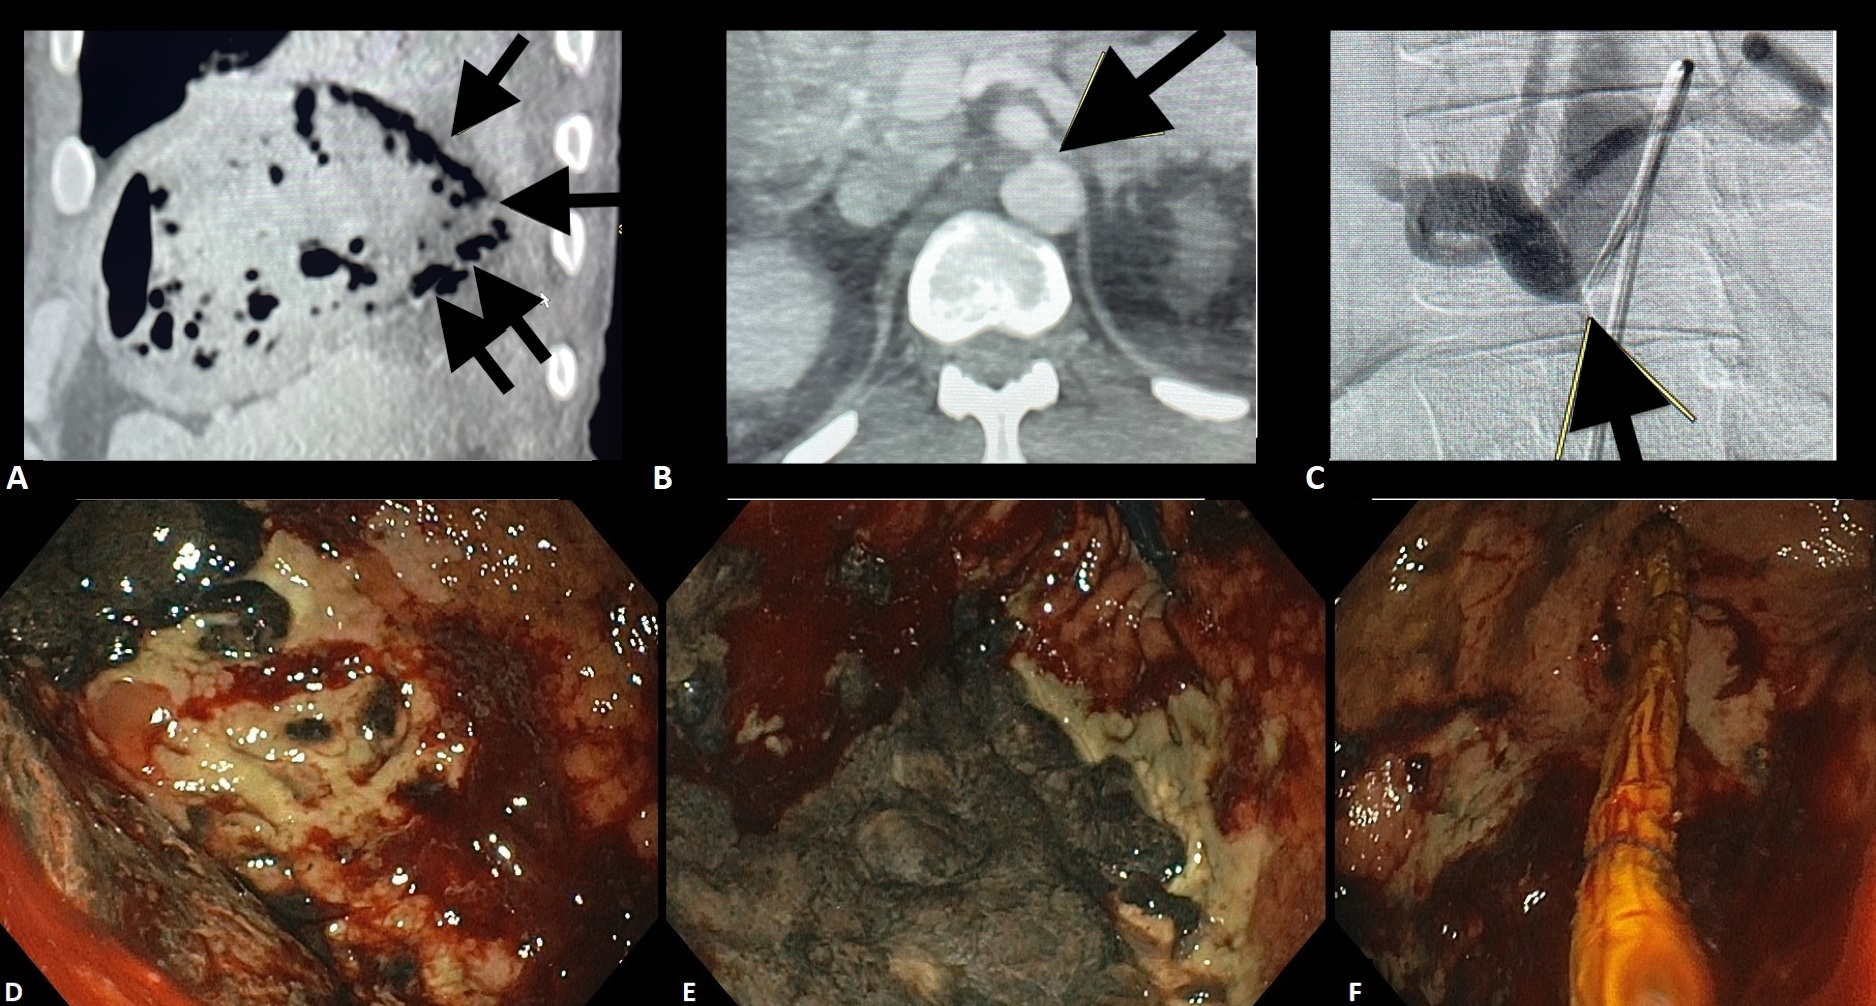

B) Procedimentos

Os pacientes randomizados para o grupo de indometacina isolada (grupo IN) receberam 100 mg de indometacina via retal imediatamente antes do procedimento. No grupo da indometacina mais prótese pancreática (grupo PP) a mesma dose de indometacina foi administrada e o endoscopista tentou ativamente a canulação do ducto pancreático principal (DPP) para a passagem da PPP, sem padronização de tempo ou técnica.